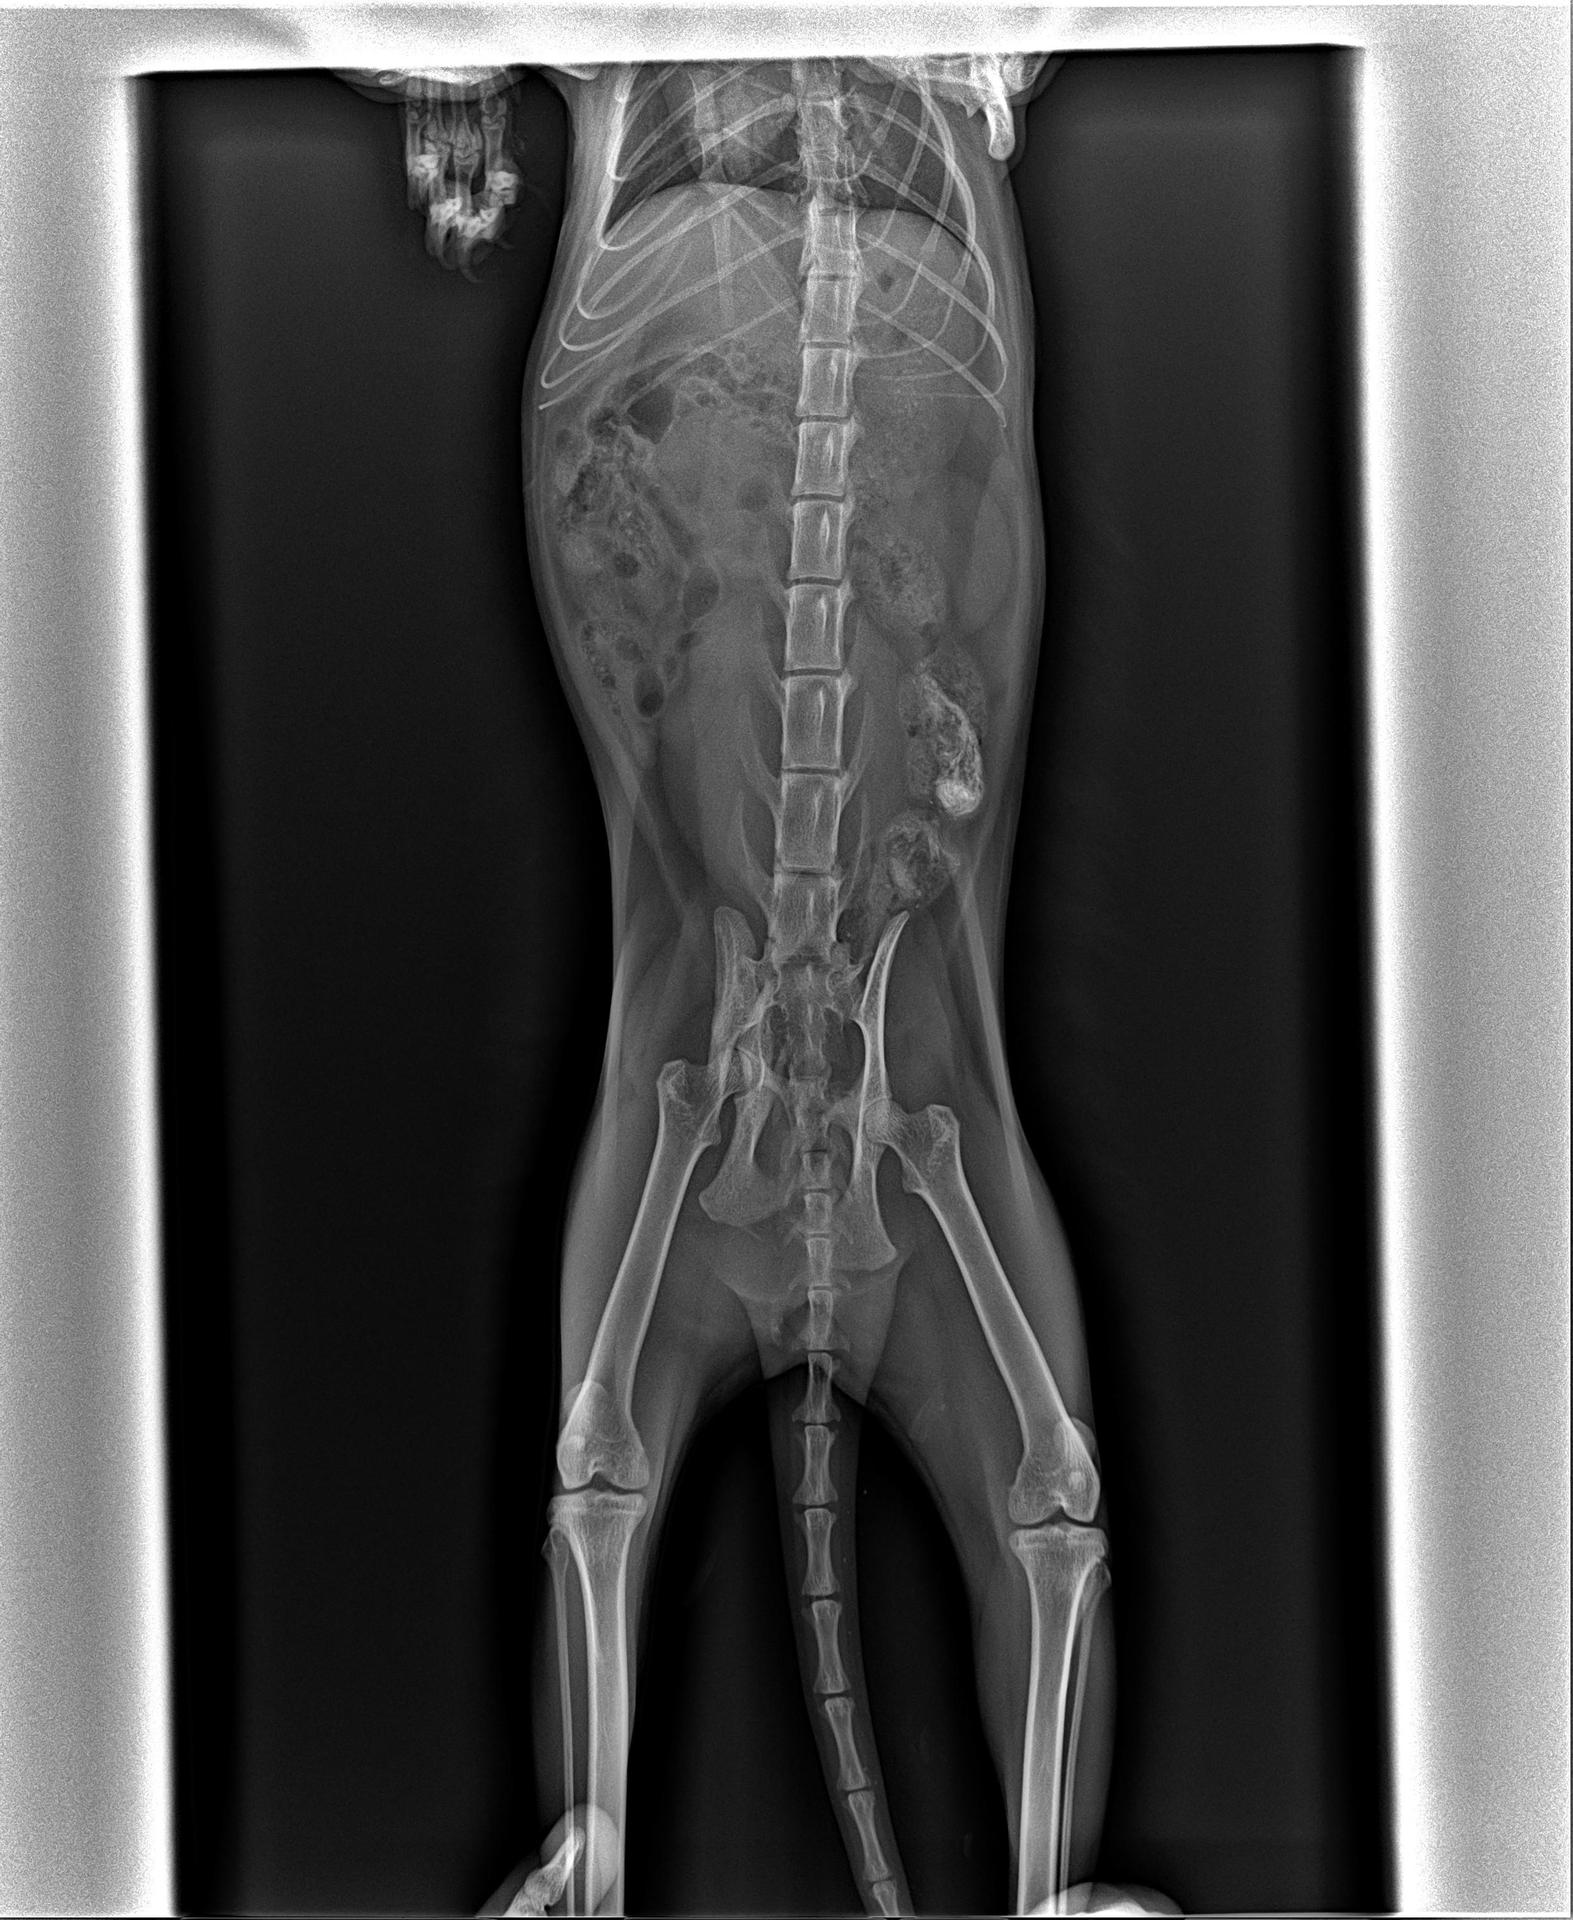

Рентгеновский эффект создает фантастические композиции в этих фотографиях девушки, чье тело становится прозрачным, демонстрируя скелет и внутренние органы. Она позирует в разных позах, ее силуэт светится загадочным свечением. Каждый кадр передает атмосферу научной фантастики и медицинского искусства. Ее кожа кажется полупрозрачной, позволяя увидеть кости и мышцы. Фотографии рассказывают о хрупкости человеческого тела и его внутренней красоте. Девушка то стоит в задумчивости, то делает грациозное движение. Эти иллюстрации вдохновляют на размышления о человеческой анатомии и уязвимости. Каждая картинка - это момент прозрения, когда внешнее уступает место внутреннему. Девушка воплощает образ современной Медузы, сочетающей красоту и загадочность.

Сквозь материю: тайны анатомии